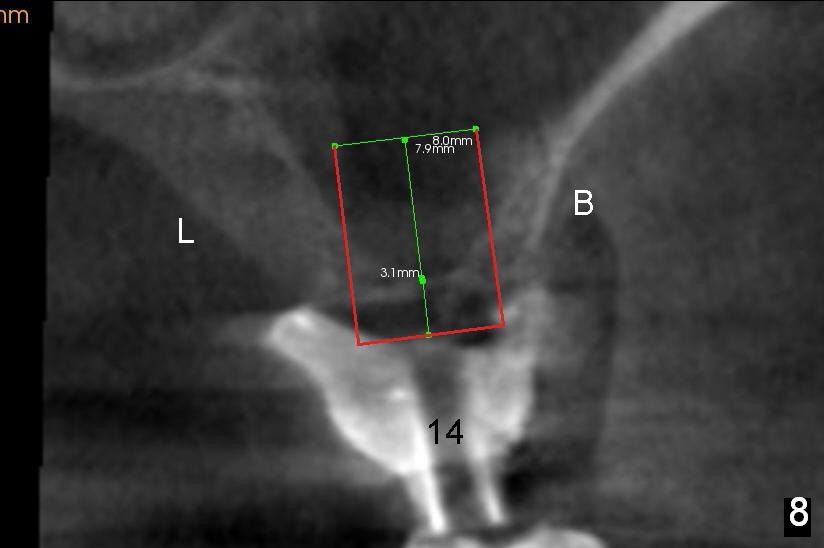

A man in his 70s had a partial denture in the upper left quadrant (Fig.1) prior to loss of #15, which was replaced by an implant (Fig.2). Lateral window sinus graft was tried without success in preparation for $14 implant placeement. Recently the partial was lost. Two missing teeth are going to be restored by implants with sinus lift in the crestal approach. Although the bone height is limited (2 mm), the implant at the site of #14 is able to obtain primary stability by engaging into the sides of the sinus floor (Fig.2 arrowheads).

After crestal incision, a 3.5 or 4 mm trephine bur is used for 2 mm at #14. The regional sinus floor is lifted using a Bicon flat-end osteotome, followed by bone graft and taps. If the 6x11 mm tapered tap does not gain stability (Fig.3), use either 6x11 mm round tap (Fig.4) or 7 or 8x11 mm tapered tap (Fig.5). If the last does not work, try a larger round tap (Fig.6). In all, the sinus floor is pushed upstairs and an implant is inserted to be engaged into the sides of the sinus floor (Fig.7).

Coronally, a round implant does not appear to obtain more bone contact than a tapered one of the same diameter (Fig.8,10). Internal sinus lift works for this case?